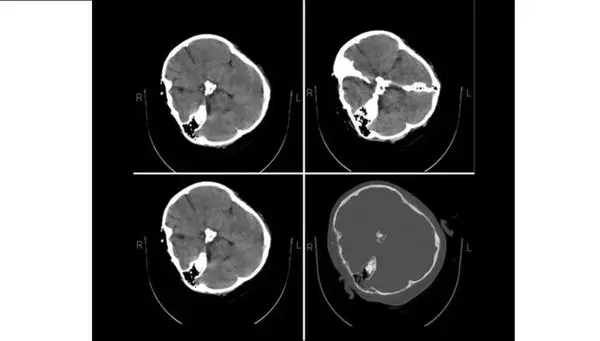

متخصصان نرورادیولژی هیأت بورد رادیولوژی وزارت بهداشت در پاسخ به استعلام ریاست سازمان نظام پزشکی درباره تصاویر «سی تی اسکن» منتشر شده از مرحوم مهسا امینی با انتشار بیانیه‌ای اعلام کردند که «هیچ شواهدی از خونریزی مغزی در این تصاویر به چشم نمی‌خورد.»

به گزارش سایت دیده بان ایران؛ متخصصان نرورادیولژی هیأت بورد رادیولوژی وزارت بهداشت در پاسخ به استعلام ریاست سازمان نظام پزشکی درباره تصاویر «سی تی اسکن» منتشر شده از مرحوم مهسا امینی با انتشار بیانیه‌ای اعلام کردند که «هیچ شواهدی از خونریزی مغزی در این تصاویر به چشم نمی‌خورد.»

در بیانیه متخصصین نرورادیولژی هیأت بورد رادیولوژی وزارت بهداشت که در پاسخ به استعلام ریاست نظام پزشکی صادر شده، آمده است: «با توجه به استعلام ریاست نظام پزشکی، متخصصین نرورادیولژی هیات بورد رادیولوژی وزارت بهدشت، پس از بررسی تصاویر سی‌تی اسکن مغز  مرحومه مهسا امینی اعلام می‌دارد در سی‌تی اسکن که به‌صورت فیلمبرداری از، مانیتور تهیه شده است، خونریزی در پارانشیم مغزی، خونریزی اپیدورال و سابدورال  دیده نمی‌شود.»